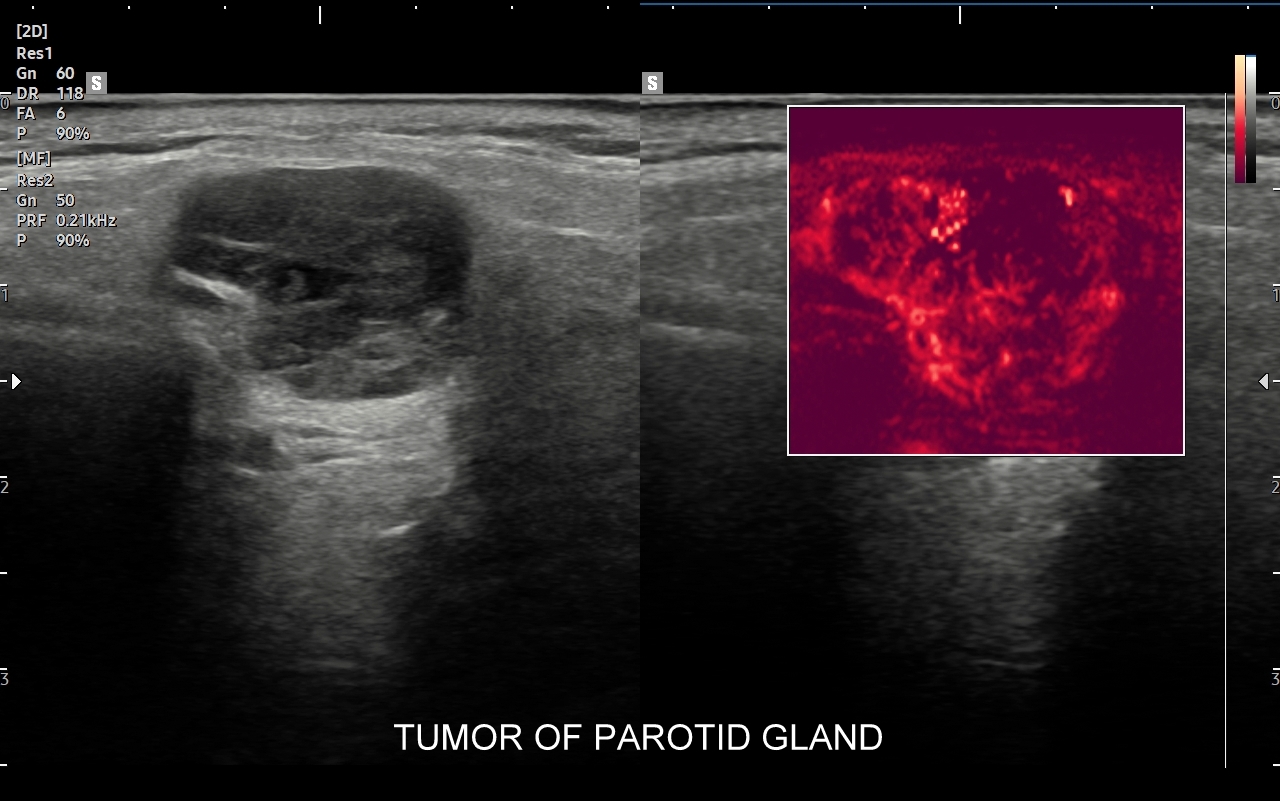

Przykładami guzów nienowotworowych w śliniankach są odczynowe węzły chłonne i torbiele. Najczęstszymi nowotworami łagodnymi są gruczolak wielopostaciowy, zwany także guzem mieszanym (tzw. tumor mixtus) oraz gruczolak limfatyczny (tzw. guz Warthina) posiadający sonograficzne cechy nowotworu lito-torbielowatego. Guz mieszany jest zmianą wolno rosnącą z tendencją do miejscowej wznowy po zabiegu chirurgicznej resekcji. Z kolei guz limfatyczny, czyli guz Warthina, częściej występuje u palaczy papierosów, może być obustronny, a ze względu na swój histologiczny charakter może pojawić się po przebyciu infekcji górnych dróg oddechowych. Wśród nowotworów złośliwych dominują rak śluzowo-naskórkowy, gruczołowo-torbielowaty i gruczolakorak. Nowotwory ślinianek najczęściej umiejscawiają się w śliniance przyusznej, a większość z nich ma charakter łagodny. W przypadku nowotworów lokalizujących się w pozostałych śliniankach częściej spotyka się guzy złośliwe.

Pacjenci ze skierowaniem na badanie USG ślinianek zgłaszają się do Pracowni zwykle w przypadku dolegliwości subiektywnych bądź obiektywnych zlokalizowanych w okolicy żuchwy i górnych partii szyi. Należy jednakże mieć na uwadze, że patologie umiejscowione w wymienionych obszarach nie zawsze odpowiadają chorobom ślinianek, a mogą dotyczyć np. węzłów chłonnych, migdałków, czy innych tkanek miękkich szyi. USG to podstawowe badanie obrazowe ślinianek. Jest procedurą bezpieczną i dokładną, a w Pracowni dr Szczepańskiego ślinianki oceniane są nowoczesną metodą MPUS (multiparametryczne USG) z zastosowaniem trybów mikrounaczynienia i elastografii. W przypadku konieczności oceny głębokich części ślinianek przyusznych albo zaplanowania operacji w obrębie szyi wykonuje się tomografię komputerową lub rezonans magnetyczny szyi.